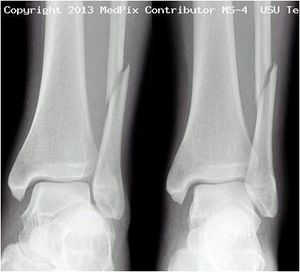

- AP: Best for isolated lateral and medial malleolar fractures

- Oblique (mortise)

- Best for evaluating for unstable fracture or soft tissue injury

- At a point 1 cm proximal to tibial plafond space between tib/fib should be ≤6mm

Classification (Danis-Weber System)

- system based on level of the fibular fracture and characterizes stability of fracture

- tibial plafond and the two malleoli is referred to as the ankle "mortise" (or talar mortise)

Type B

- fibula fracture at the level of the ankle joint/at the plafond

- can extend superiorly and laterally up fibula

- tibiofibular syndesmosis intact or only partially torn

- no widening of the distal tibiofibular articulation

- medial malleolus may be fracture

- possible instability

Type C

- fibula fracture above the level of the ankle joint/proximal to plafond

- tibiofibular syndesmosis disrupted with widening of the distal tibiofibular articulation

- medial malleolus fracture

- unstable: requires ORIF